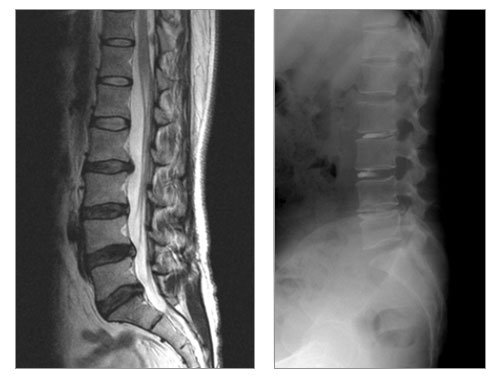

- MRI(ÀÚ±â°ø¸í¿µ»ó)